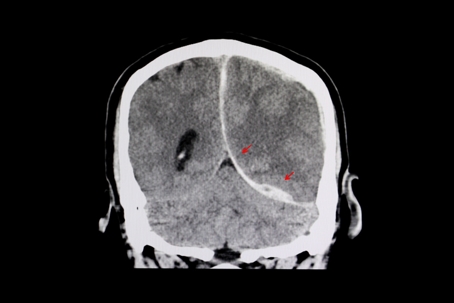

Is A Brain Injury Permanent? Understanding Long-Term Effects After a Fort Myers Car Accident

TBI Brain Scan